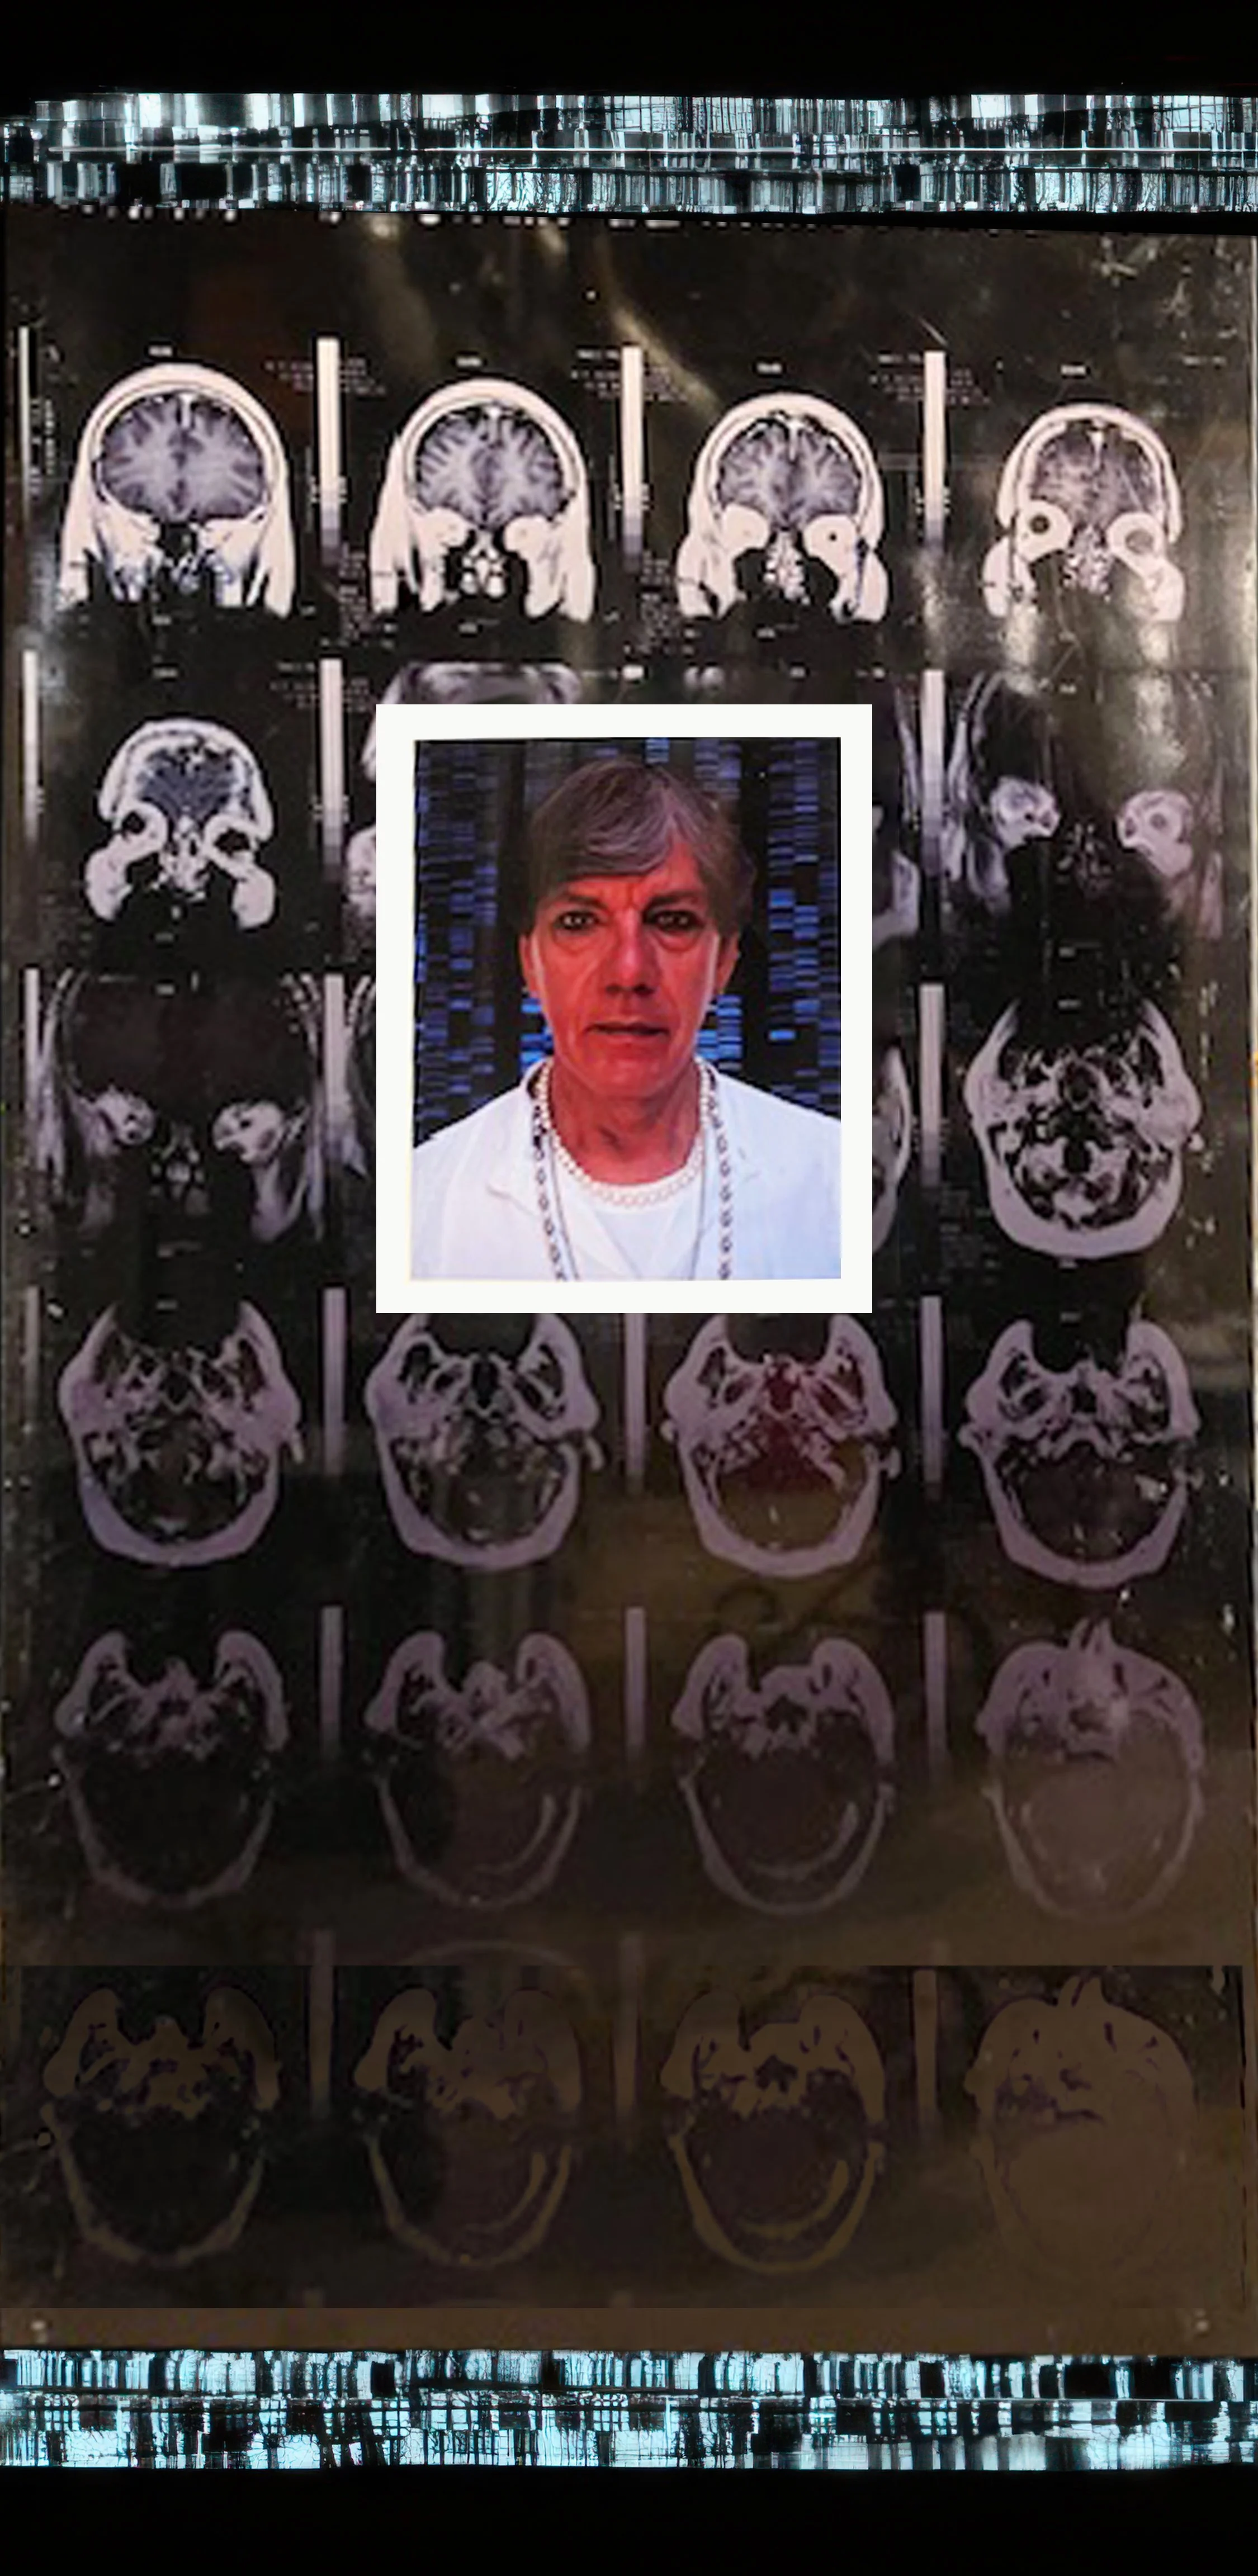

Comprising eight 47” x 23” backlit Plexiglas panels, each work features a portrait, often of individuals from diverse racial, ethnic, and cultural backgrounds. Surrounding these portraits are embedded CT scans, MRIs, and DNA sequencing gels. These medical images, reimagined as expressive symbols, evoke biological inheritance, invisible histories, and interior experience rather than clinical diagnosis.

Used metaphorically, DNA strands suggest ancestral continuity; CT scans and MRIs hint at the unknowable workings of body and psyche; ghostly anatomical forms recall trauma, resilience, and emotional scars. By pairing portraiture with interior imaging, the series questions how we perceive identity. Are we defined by surface appearance—skin, gender, dress—or by memory, genetics, and lived medical experience? Can scientific data be truly neutral, or does it reflect cultural bias and interpretation?

Bald Man 47” x 23”